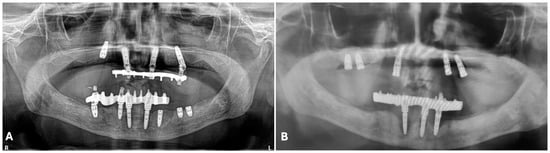

2. Case Description